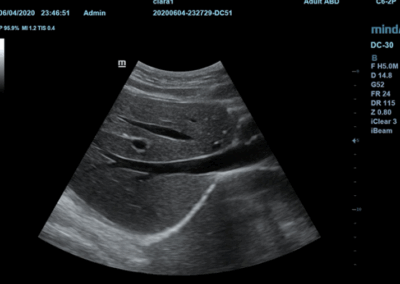

DC-30FULL HD

Sistema de diagnóstico ecográfico.

Los sistemas ecográficos estándares disponibles en la actualidad generalmente permiten un diagnóstico básico, pero carecen de funcionalidades avanzadas. Ahora, el DC-30 FullHD es la respuesta perfecta para un rendimiento de imagen de alta calidad, con una pantalla táctil de 21,5 pulgadas y funciones avanzadas como Auto IMT, iScape, elastografía Natural Touch, imágenes con contraste UWN e imágenes Doppler tisulares en el ámbito de las imágenes generales, y Smart OB, Smart face e iLive en el ámbito de la obstetricia.